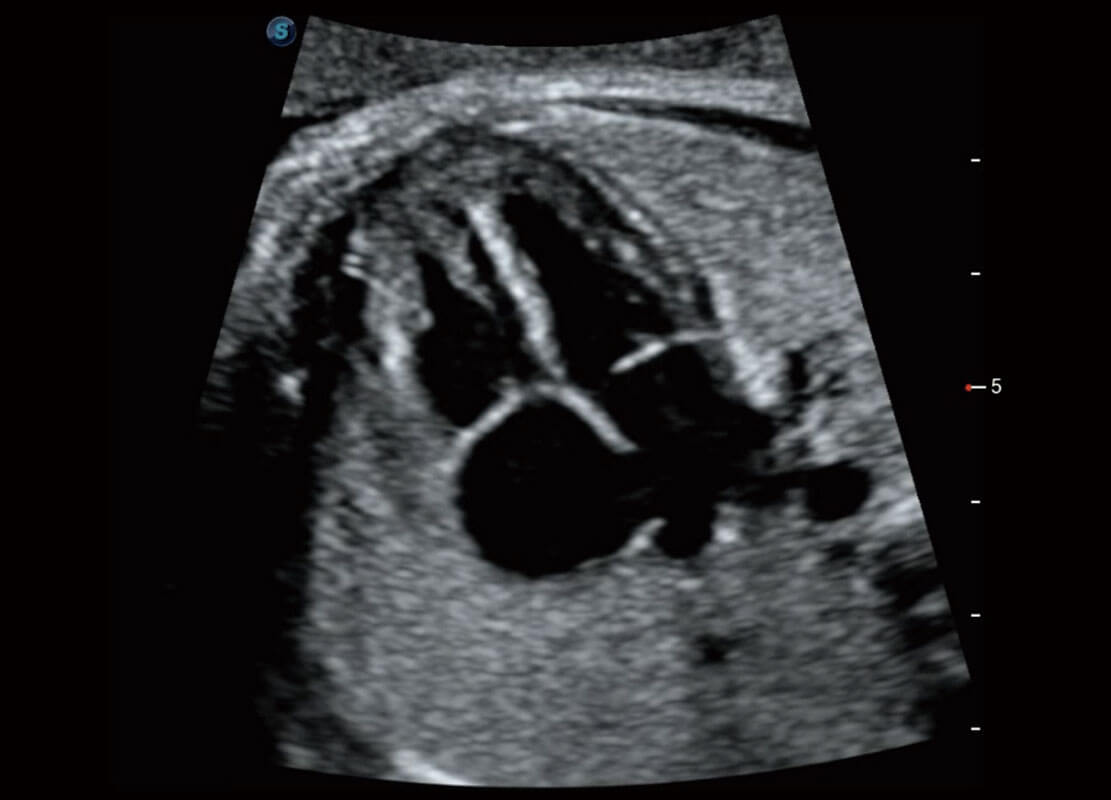

新生儿肝血管癌

新生儿脊髓圆锥

新生儿心脏